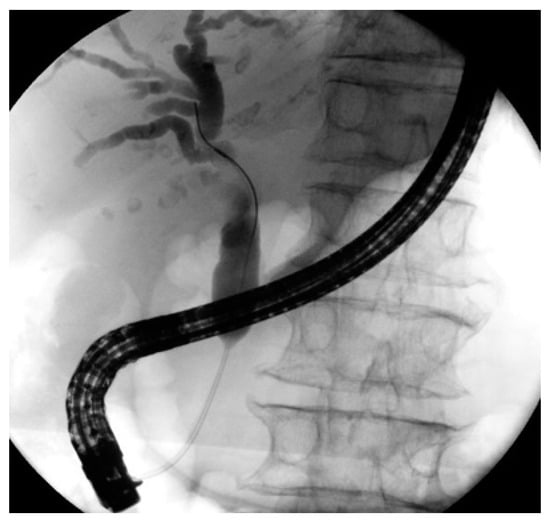

3.1. ERCP

4.1. ERCP in Distal Strictures

4.2. ERCP in Perihilar Strictures